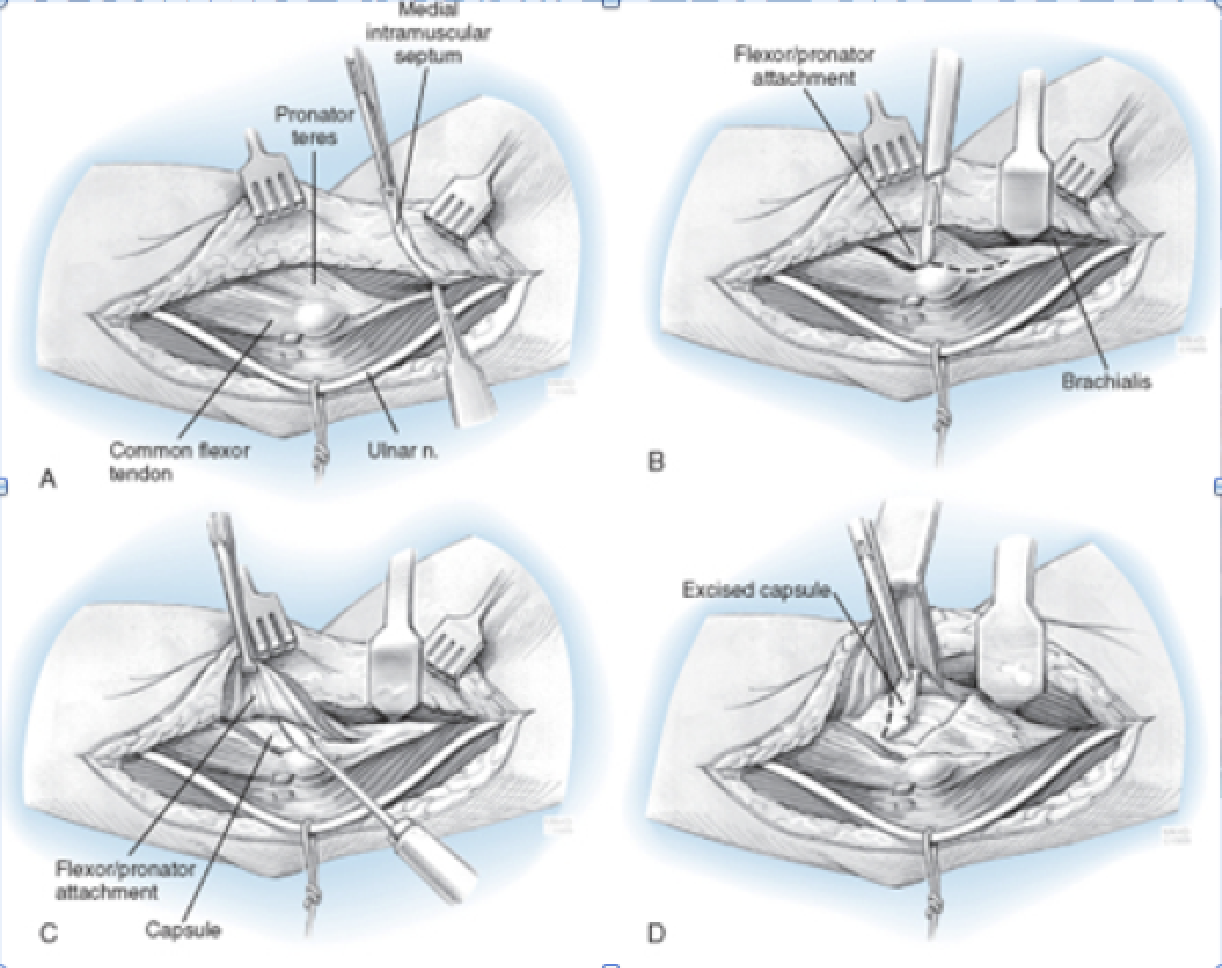

Hotchkiss Medial Over-the-top

Interval:

- Proximally: Intermuscular septum between triceps (radial n.) & brachialis (radial n, median n.)

- Distally: Through flexor pronator mass. FCU (ulnar n.) & FDS/Palmaris Longus (Median n.)

Approach: Unroof, identify and mobilize the ulnar n. Split flexor pronator mass, and elevate anteriorly. Care to be taken for MUCL

Dangers: Ulnar N. MUCL, Median N. Brachial A., MABCN (found on fascia anterior to septum)